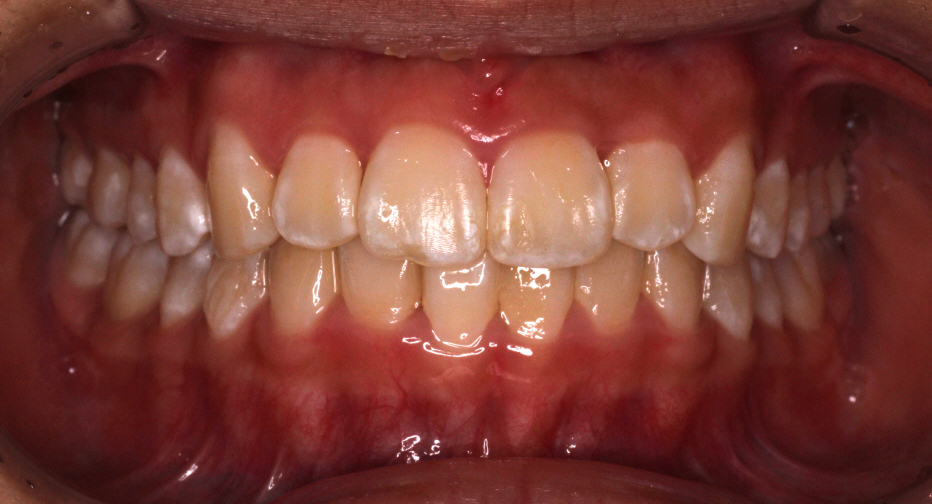

最後のアライナーが終わった時の口腔内写真です。

前歯のがたつきはなくなり、カリエール後にできていた隙間もなくなっています。

奥歯も1歯対2歯の関係で咬めていることがわかります。

通常は歯の並びを微調整するために口腔内を再スキャンし、歯の並びを再設計すること(リファイメント) を2,3回行いますが今回のケースは一回目で満足のいく結果が得られたのでここで保定期間に入りました。

患者様には気にされていた歯のでこぼこがなくなり、喜んでいただきました。

矯正にかかった期間はなんと1年です。